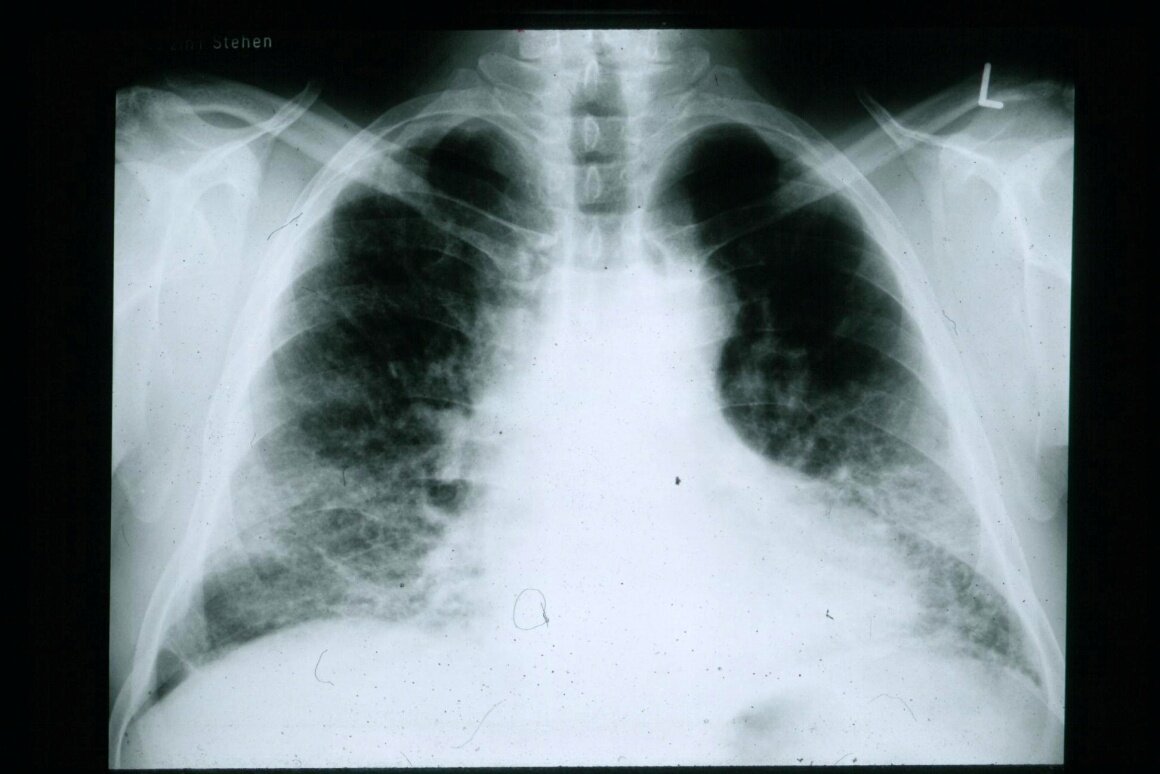

После приема пищи начинает активную работу пищеварительная система. Слизистая оболочка желудка, поджелудочная железа и кишечник начинают выделять многочисленные пищеварительные ферменты. Нужна энергия для того, чтобы протолкнуть пищу по пищеварительному тракту. Затем переработанные ферментами белки, жиры и углеводы всасываются в кровоток. В связи со всеми этими процессами необходим приток к органам пищеварительной системы большого количества крови. Кровоток в организме человека перераспределяется. Кишечник получает больше кислорода, остальные органы – меньше. Если организм работает нормально, то при этом не отмечается никаких нарушений. Если же имеются какие-то заболевания и отклонения, то во внутренних органах развивается кислородное голодание, а легкие, стремясь устранить его, начинают работать в усиленном темпе. Появляется одышка. Если у вас возникает одышка после еды, то нужно явиться на прием к терапевту для того, чтобы пройти обследование и разобраться в ее причинах.